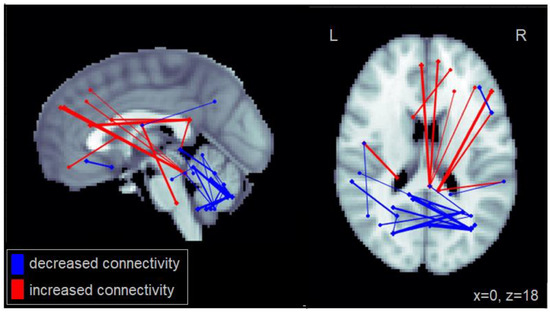

Similarly, increased steering variability (SD in steering) among patients with MCI was associated with increased connectivity between the right PCC and the right frontal gyrus as well as the right middle temporal cortex (Figure 3). Increased steering variability was also associated with reduced connectivity between cerebellar regions. This number of significantly reduced intra-cerebellar connections for steering variability was greater than that observed for lane deviations. Furthermore, increased steering variability was associated with reduced connectivity between the cerebellum and the middle and inferior temporal cortex. The complete set of regions showing alterations in connectivity among patients with MCI related to increased lane deviations is reported in Table A3.

Figure 3.

Altered functional connectivity associated with standard deviation in steering observed among patients with MCI. Blue lines denote functional connections with reduced connectivity associated with greater lane deviations, red lines denote increased connectivity (significant at FDR = 0.05). Connections are shown as projections in the sagittal and axial plane, with MNI anatomical underlays (slices at x = 0 and z = 18 respectively).